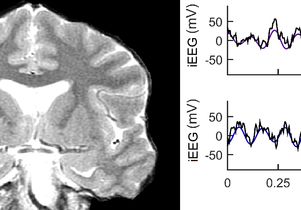

UCLA neuroscientists use weak electrical signal to stimulate human brain and improve memory October 24, 2017 UCLA ...